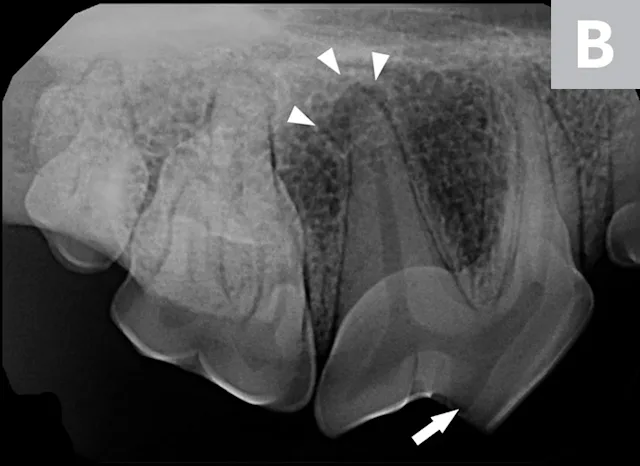

Patient positioned in lateral recumbency; the bisecting angle technique is used to obtain radiographs of the right maxillary fourth premolar (A). The plate or film should be parallel to the hard palate (white line). The direction of the tooth root to be imaged is represented by a black line. An imaginary line can be drawn halfway between the angle of the plate or film and tooth roots (ie, bisecting angle [gray line]), usually a 45-degree angle for the maxilla. The beam (ie, x-ray tube head) should be oriented perpendicular to the bisecting angle (gray line) so the actual size of the tooth is shown (B); a crown fracture with suspected pulp exposure is visible (arrow), and radiolucency can be seen around the apex of the distal root (arrowheads).